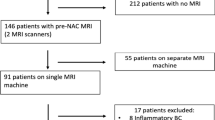

This monocentric retrospective study included 75 TN female patients with MRI (T1-weighted, T2-weighted, diffusion-weighted and dynamic contrast enhancement images) performed before NAC. For each patient, the tumor(s) and the parenchyma were independently segmented and analyzed with radiomic analysis to extract shape, size, and texture features. Several sets of features were realized based on the 4 different sequence images. Performances of 4 classifiers (random forest, multilayer perceptron, support vector machine (SVM) with linear or quadratic kernel) were compared based on pathological complete response (defined on the excised tissues), on 100 draws with 75% as training set and 25% as test.